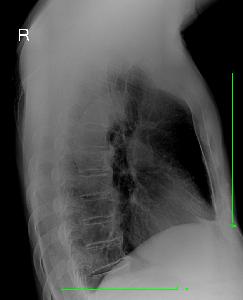

男,25岁,咳嗽伴右侧胸痛一周。各位同仁看看是什么病,请大家发表自己的观点,谢谢大家。 阅读全文>